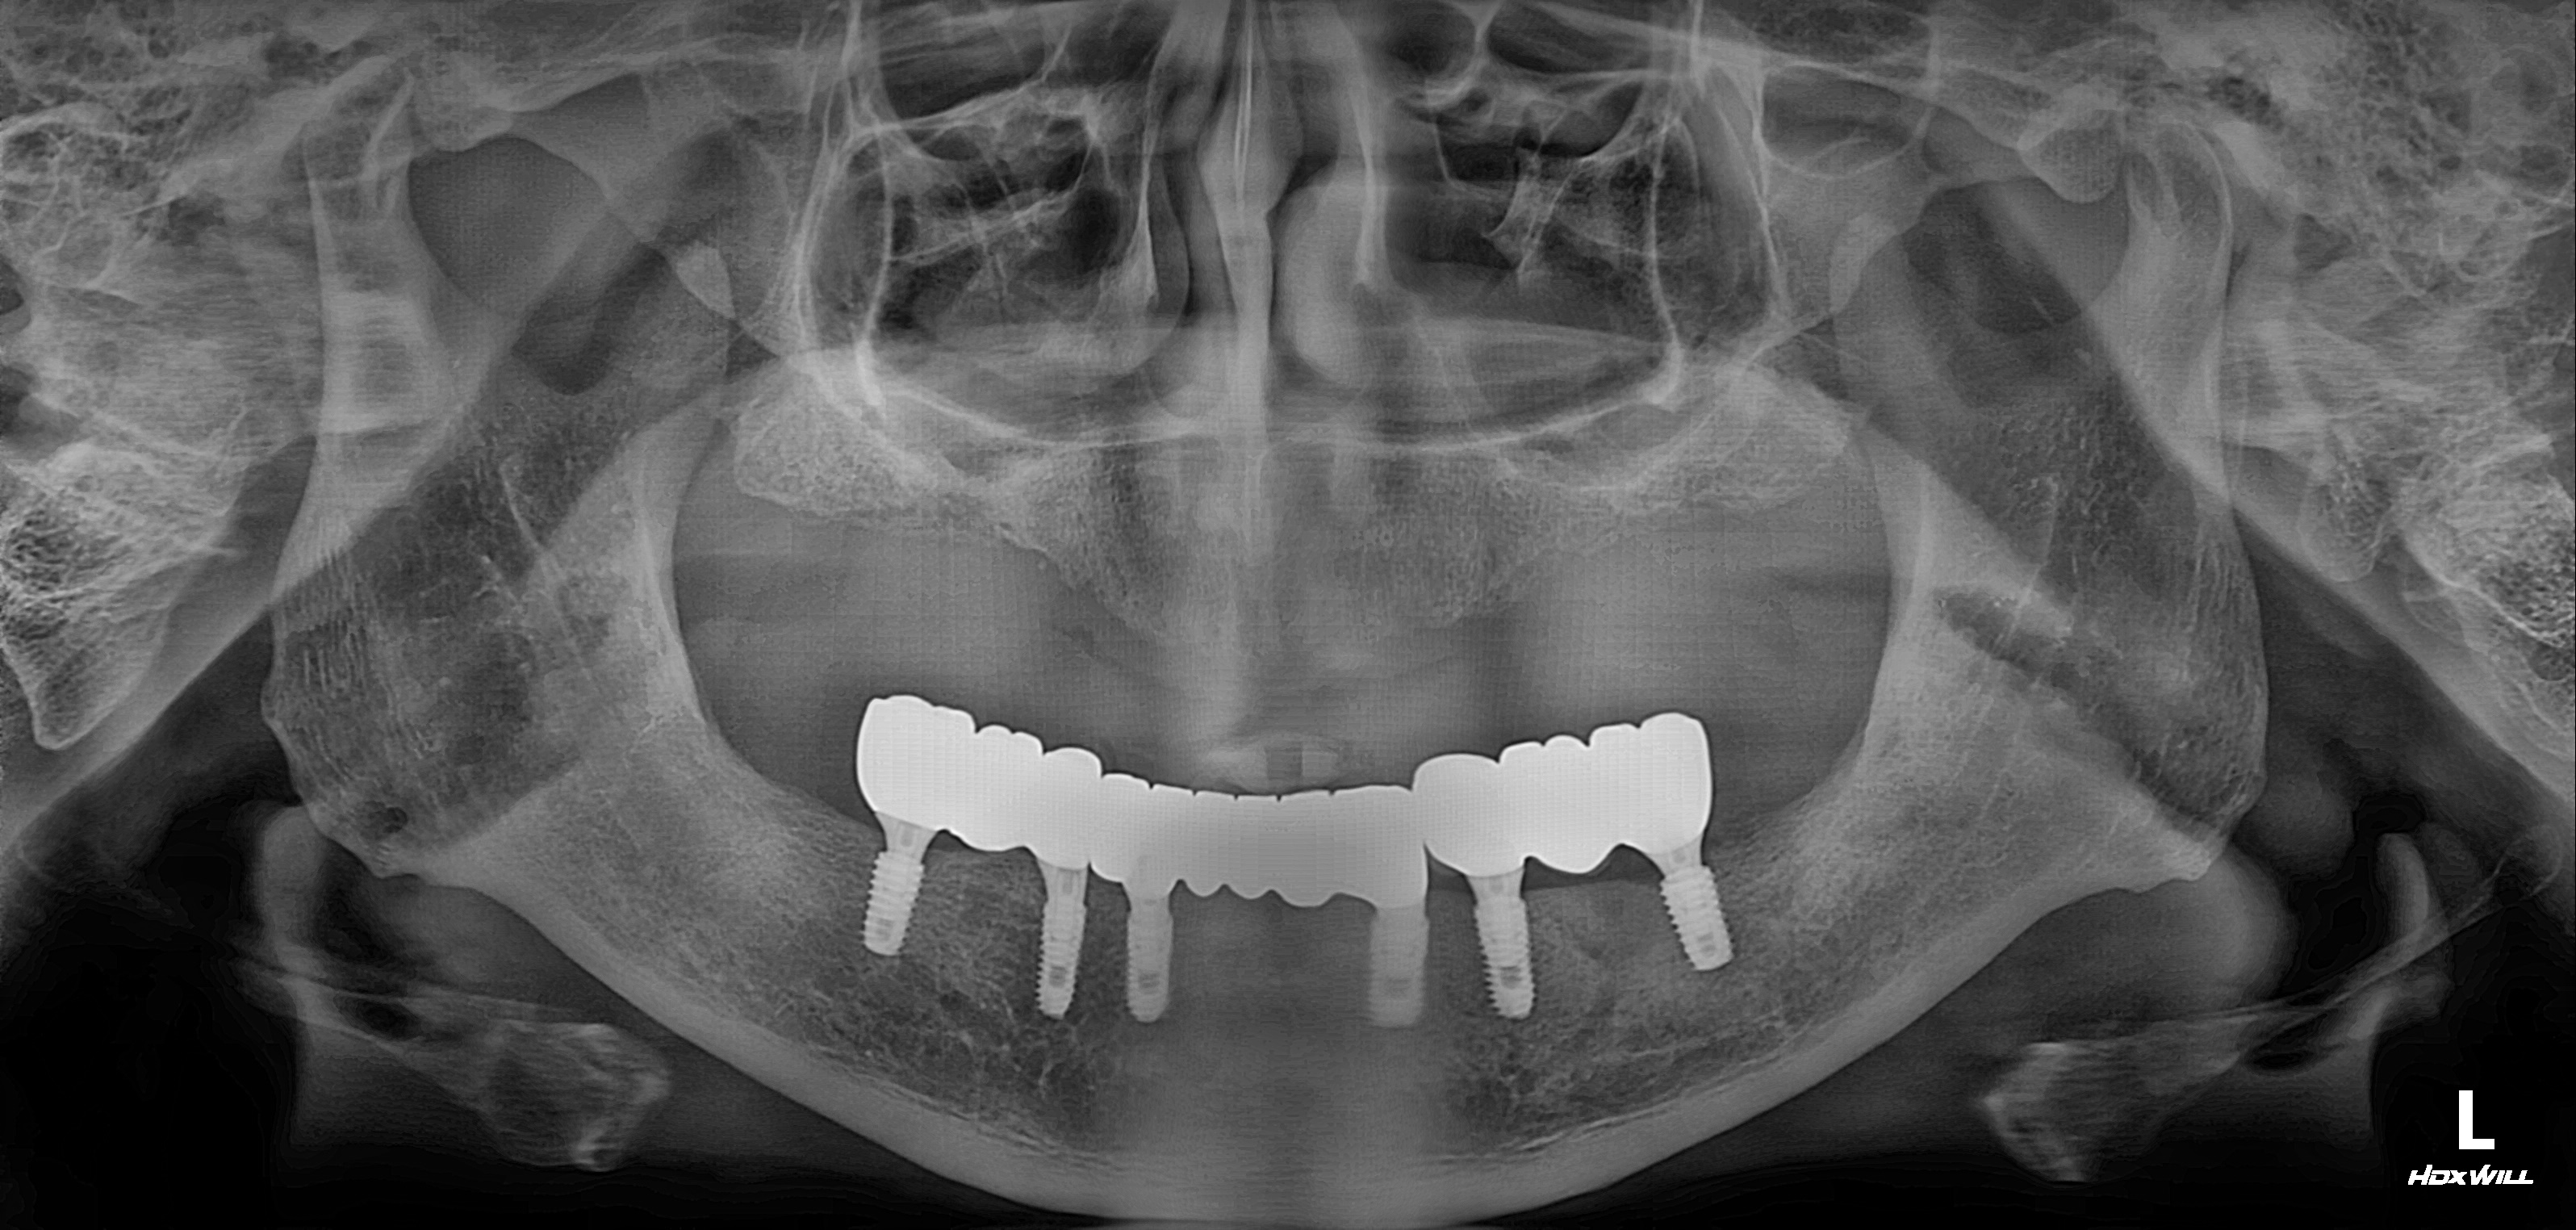

수술 전

수술 후

전악임플란트 식립사례

전후사진